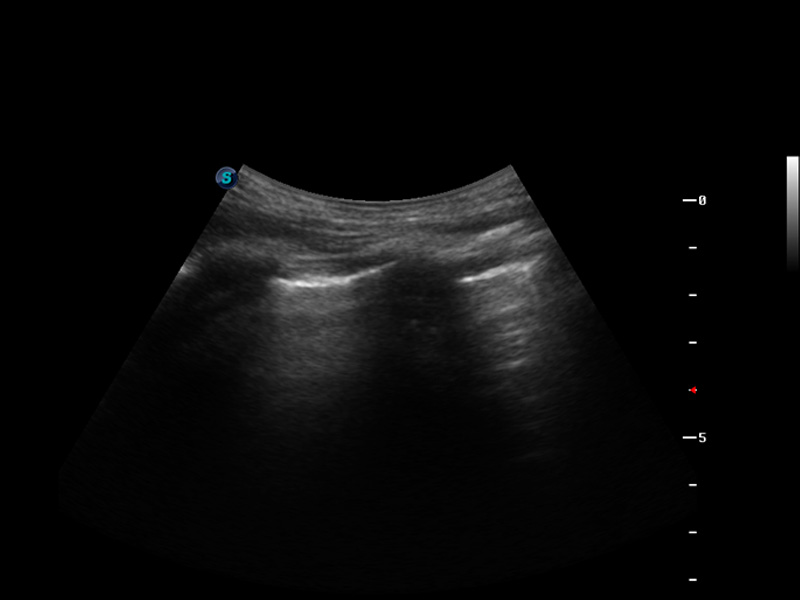

S9便携式彩色多普勒超声诊断仪是诸侯快讯官网研发的高端便携彩超设备,外观设计新颖、产品性能卓越。S9在便携超声领域采用了突破传统的触摸屏交互设计,并以先进的软件硬件技术和设计理念,为您带来清晰的图像质量、稳定的工作性能和便捷的操作体验。

脉冲反相谐波成像